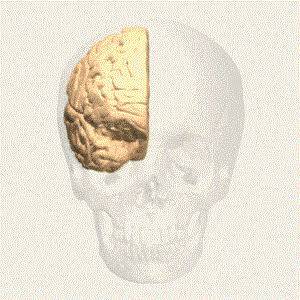

De twee HEMISFEREN

WAT IS EEN HERSENINFARCT

Degrote hersenen bestaan uit twee hersenhelften(hemisferen). Grofweg speelt de rechterhersenhelft een rol bij non-verbale zaken,de linkerhersenhelftmeer met verbale zakenl. Grofweg stuurt de rechterhersenhelft de linkerkant van het lichaam aan en omgekeerd.bij een halfzijdige verlamming aan de linkerkant van het lichaam, wat bij mij het geval is,heeft er een beroerte in de rechterhersenhelft plaatsgevonden

DE TWEE HEMISFEREN(hersenhelften)